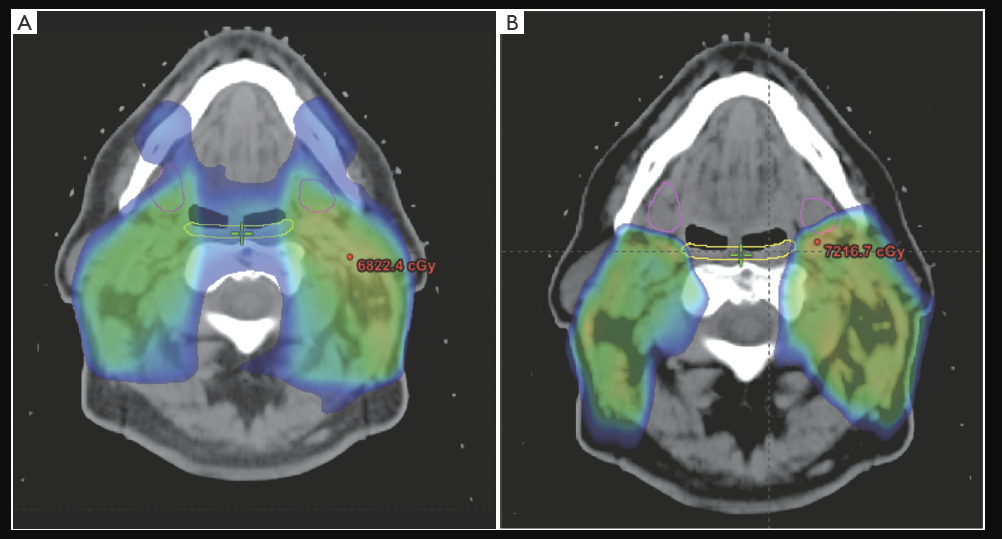

▲质子治疗晚期喉癌患者,图源:[2]